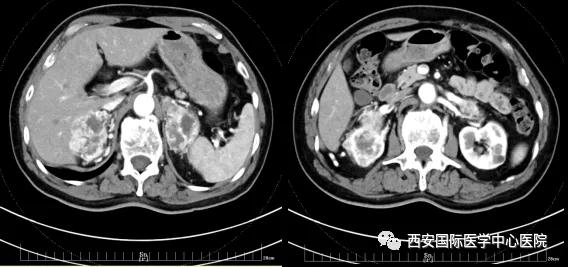

今年七十五歲的患者,來(lái)自陜西省商洛市,四月前因腰背部疼痛就診于當(dāng)?shù)蒯t(yī)院,行CT檢查發(fā)現(xiàn)“右腎、雙側(cè)腎上腺占位,前縱膈淋巴結(jié)腫大,雙肺多發(fā)結(jié)節(jié)、胸椎骨質(zhì)破壞,考慮轉(zhuǎn)移瘤”。為進(jìn)一步診斷治療,患者的兒子帶他來(lái)到西安某三甲醫(yī)院,查泌尿系CT提示“右腎占位性病變,多考慮腎癌,雙側(cè)腎上腺多發(fā)轉(zhuǎn)移灶,腹膜后多發(fā)腫大淋巴結(jié)”;行穿刺活檢提示“腎透明細(xì)胞癌”;并給予患者口服靶向藥物的治療方案。

自四月份至今,患者一直口服靶向藥物治療(阿昔替尼5mg 2次/日),期間無(wú)不良反應(yīng),目前腰背部疼痛癥狀也有所緩解,復(fù)查影像學(xué)資料提示瘤體較前縮小,腫瘤完整切除的可能性明顯提高;而且患者的兒子也是一名外科醫(yī)生,所以他更想為父親完成后續(xù)的手術(shù)治療。

手術(shù)由楊增悅教授主持,舒濤主治醫(yī)師、王東主治醫(yī)師主刀,黃怡醫(yī)師、王平醫(yī)師協(xié)助完成。由于第四代達(dá)芬奇機(jī)器人更加靈活和精準(zhǔn)的特性,手術(shù)全程順利,尤其是完全精準(zhǔn)的“解鎖”了右腎動(dòng)脈和右腎靜脈的數(shù)十根交互纏繞的分支血管。術(shù)后患者麻醉恢復(fù)后生命體征平穩(wěn),順利返回泌尿外科普通病區(qū)進(jìn)一步康復(fù)。